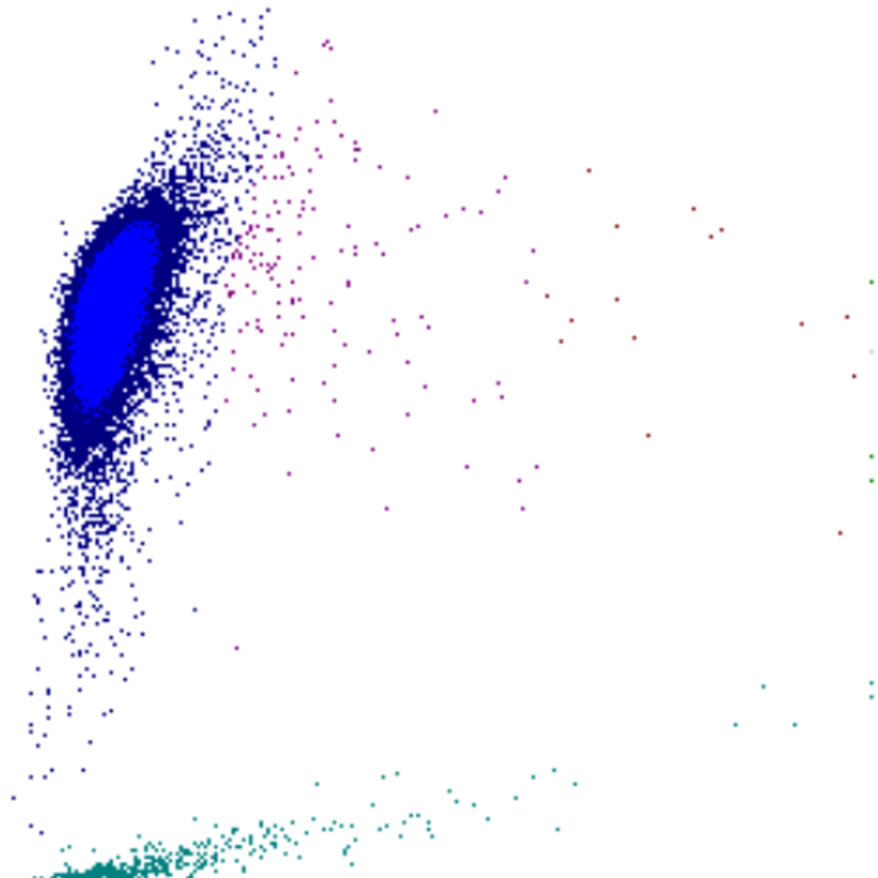

Side Scatter

La complexité cellulaire est principalement déterminée par la présence de structures intracellulaires telles que les granulations. Dans une moindre mesure, la forme du noyau (lobulation) et la présence de vacuoles jouent également un rôle. Dans le canal WDF du Sysmex, les éosinophiles présentent un SSC plus élevé que la normale en raison de l’effet du réactif sur leur granulation.

SSC scatter

SSC faible

SSC élevé